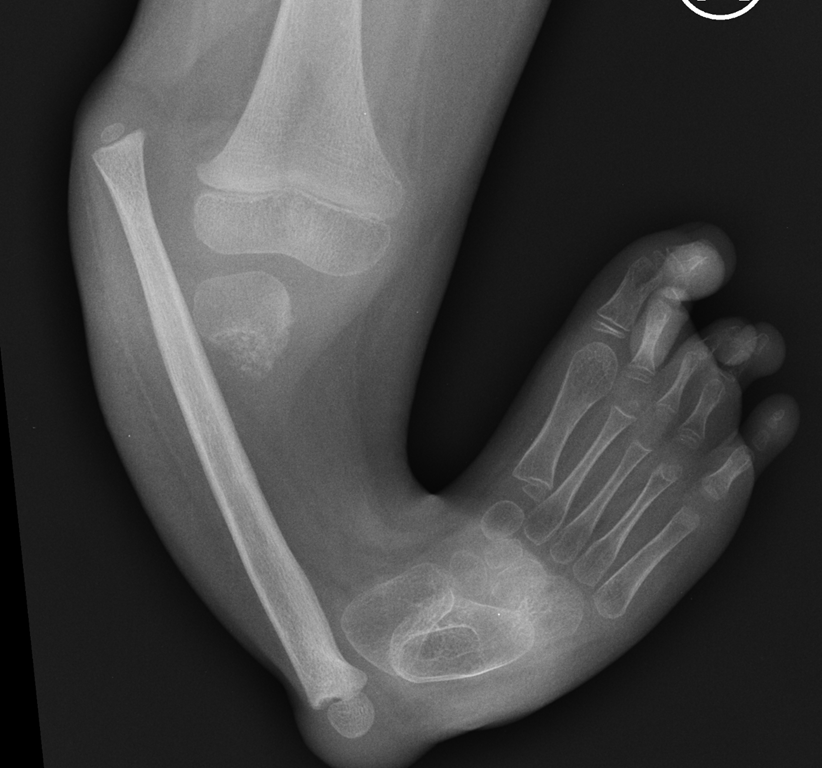

Dziewczynka urodziła się ze zniekształconą kością piszczelową. Jej noga była krótsza i wygięta pod nienaturalnym kątem. Lekarze ze Szpitala imienia Wiktora Degi przeprowadzili nowatorską operację. Najpierw zrekonstruowali stawy: kolanowy i skokowy, a później zaczęli wydłużać kość. Dzieci z taką wadą rodzą się jedno na milion - mówi dr Milud Shadi.

Taka wada jest bardzo ciężka. Dziecko nie ma jeszcze czterech lat i już ma skróconą nóżkę o 12 cm. Do tego nieprawidłowe kolano, nieprawidłową stopę. Dziecko jeszcze ma aparat zewnętrzny na nodze, który planujemy za miesiąc usunąć. Ona chodzi w aparacie i ma wyrównywaną nogę. Jakbyśmy nic nie robili, to w wieku dojrzałości - dla dziewczynki 14 lat - to to skrócenie nogi by było 25 cm.

Dziewczynkę czekają jeszcze zabiegi w poznańskiej klinice. Zakończą się, gdy przestanie rosnąć. Czterolatka dostała też specjalne białko na silny zrost kości. Czeka ją także rehabilitacja.